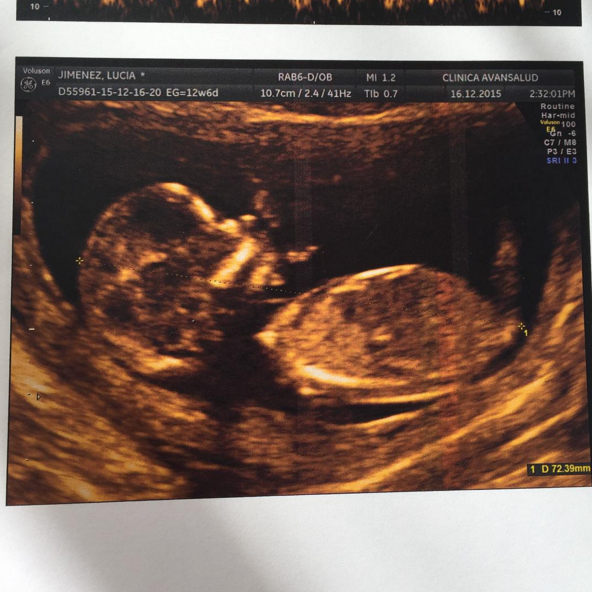

Fue así como sorprendió a sus amigos y fanáticos, cuando anunció una emocionante noticia que la tiene feliz: Lucía está embarazada de su primer hijo junto a su nueva pareja. “Tantas emociones y sentimientos que No se cómo explicarlo, ya quiero tener aquí a mi ladito mi baby” (sic), escribió la joven de 22 años junto a la imagen de una ecografía donde se puede apreciar la criatura.